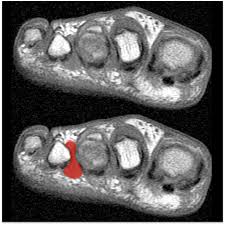

Ulcera isquemica

ulcera neuropática